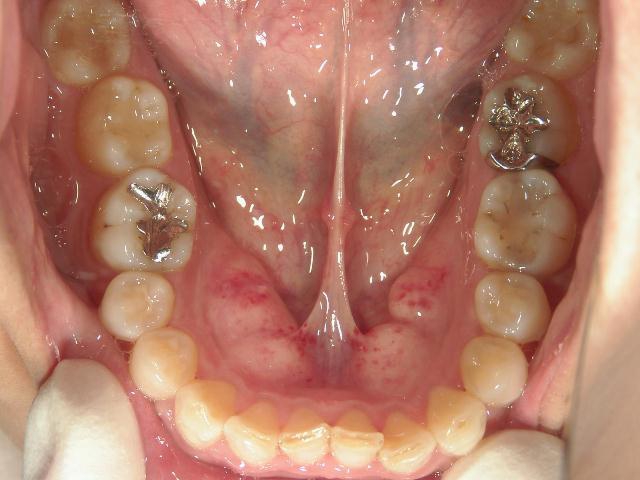

矯正歯科 治療前

全顎ワイヤー矯正 症例(2)

36歳女性 磐田市

在住

治療期間2年6

ヶ月